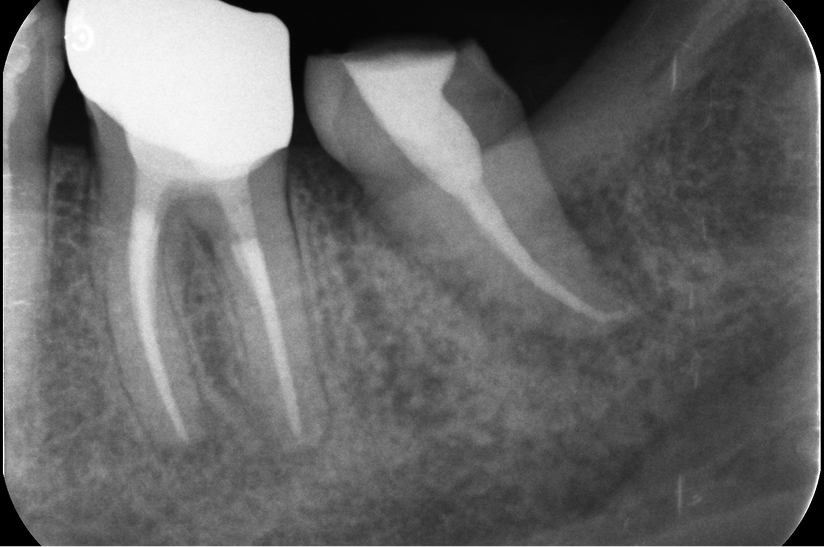

Before

Under Treatment

After

主訴

インプラントはできないが、入れ歯もしたくない

治療内容

自家歯牙移植 / イニシャルトリートメント(大臼歯)レジンコア

治療期間

3ヶ月

治療費用

550,000

治療の

リスク

術後しばらくしてから骨性癒着、外部吸収を起こす可能性があります。